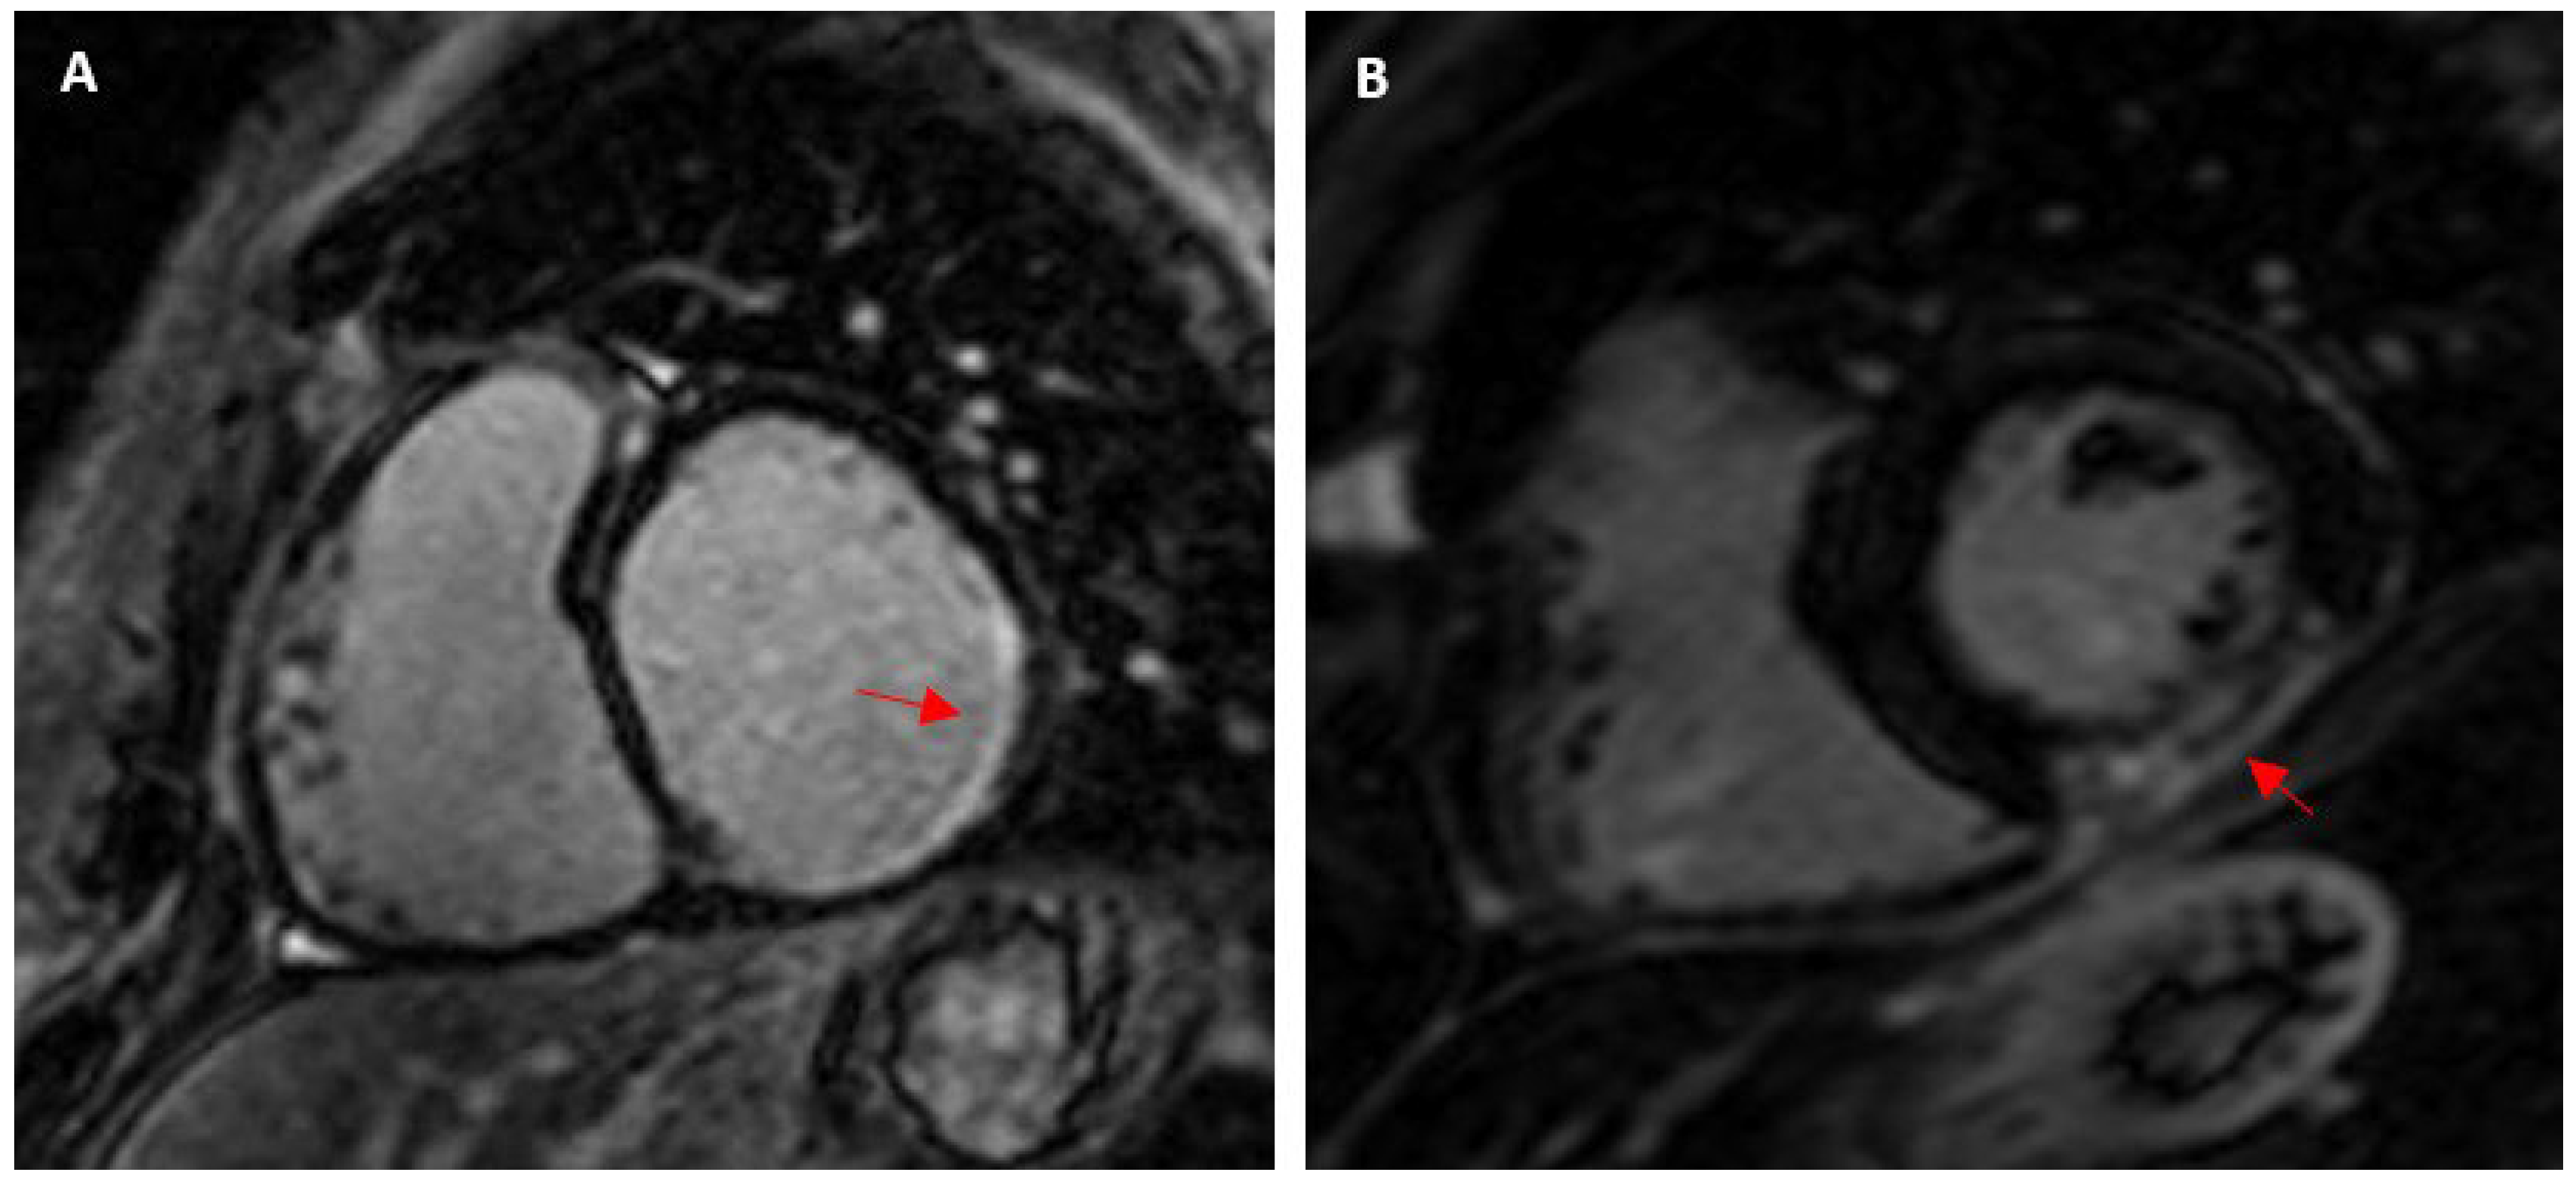

4.1. Myocardial Fibrosis in Athletes and the General Population

4.2. Factors Associated with Myocardial Fibrosis in Athletes

4.2.2. Pressure Overload

- De Bosscher, R.; Claeys, M.; Dausin, C.; Goetschalckx, K.; Bogaert, J.; Van De Heyning, C.; Ghekiere, O.; Herbots, L.; Claus, P.; Kalman, J.; et al. Hinge point fibrosis in athletes is not associated with structural, functional or electrical consequences: A comparison between young and middle-aged elite endurance athletes. Eur. Heart J. 2020, 41, ehaa946.3126. [Google Scholar] [CrossRef]

- Grigoratos, C.; Pantano, A.; Meschisi, M.; Gaeta, R.; Ait-Ali, L.; Barison, A.; Todiere, G.; Festa, P.; Sinagra, G.; Aquaro, G.D. Clinical importance of late gadolinium enhancement at right ventricular insertion points in otherwise normal hearts. Int. J. Cardiovasc. Imaging 2020, 36, 913–920. [Google Scholar] [CrossRef] [PubMed]

- Schnell, F.; Claessen, G.; La Gerche, A.; Bogaert, J.; Lentz, P.-A.; Claus, P.; Mabo, P.; Carré, F.; Heidbuchel, H. Subepicardial delayed gadolinium enhancement in asymptomatic athletes: Let sleeping dogs lie? Br. J. Sports Med. 2016, 50, 111–117. [Google Scholar] [CrossRef]